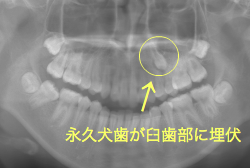

牽引(埋伏犬歯を牽引した症例)

埋伏歯とは、骨または歯茎の下に埋まって出てこない状態の歯のことを言います。埋伏歯があると歯が押されて歯並びが悪くなってしまったり、永久歯が生えてこれない原因になる恐れがあります。

「乳歯が生え替わらない」という主訴で来院したケースです。 診断の結果、「左上永久犬歯が第一小臼歯後方上部に埋伏しているため、左上乳犬歯が晩期残存している症例」と判明しました。

このような症状の場合は、手術で埋伏している永久歯に金具を取り付け、矯正装置で牽引する必要があります。同時に凸凹の解消と前突した前歯を内側に入れるために上下左右の小臼歯を抜歯させて頂くことといたしました。

この方の場合は、マルチブラケット装置にて治療を開始し、治療期間2年3ヶ月で終了しました。犬歯の牽引距離が非常に大きかったため当院の平均治療期間よりも大幅に期間がかかりましたが、埋伏犬歯を完全に正しい位置まで誘導することができました。同時に 前歯の前突と配列の凸凹も解消しました。

このような症例は、成人してしまうと埋伏歯の反応性が悪く、あまりにも動きが悪い場合は牽引をあきらめて抜歯する場合もあります。歯科医院の検診で親知らず以外の埋伏歯を指摘された場合は、できるだけ早く矯正専門医に御相談下さい。